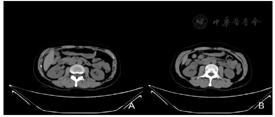

病例1专科检查:双肾区无隆起,双肾及输尿管移行区无叩压痛,膀胱区不充盈、无压痛,外生殖器无异常,尿道外口无脓性分泌物。2020年6月23日超声检查,超声所见:双侧肾上腺部位多断面超声扫查,未见明显异常回声。肾脏:右肾长108 mm;左肾长108 mm。双肾形态正常,肾实质与肾窦比例正常,肾盂、肾盏未见明显扩张。右肾下极皮质见一囊实混合性回声,大小约34 mm×31 mm×30 mm。形态规则,边界清晰,内见多发点状强回声,内未见明显血流。输尿管:双侧输尿管不扩张。超声提示:右肾囊实混合性回声,复杂囊肿?2020年6月26日,多排CT腹部平扫(中,下腹)组合,CT所见:右肾下段腹侧见结节状稍低密度影,直径约2.5 cm,其内见斑点状钙化灶。左肾大小、形态正常,两肾实质内未见异常密度灶,双侧肾盂、肾盏及输尿管无明显扩张积水征象,内无异常密度影。肾周脂肪间隙清晰。双侧肾上腺形态、大小未见明显异常(图1)。

2020年6月29日多排CT肾肿瘤CTA(优维显)。CT所见:右肾中下极前部可见一约2.8 cm×2.1 cm×2.7 cm大小的低密度灶(T),内见少许分隔,病灶边界尚清,局部膨出于肾脏表面。右肾动脉提前发出一支分支至右肾上极;远端发出上、下两分支:上支继而发出前、后两支"上-前支远段至右肾中上极前部;上-后支远段至右肾中上极后部"。下支在肾门处发出前上、后下两分支:下-前支(A)先发出一小分支进入病灶(T),继而发出前、后两支:下-前上-前支远段进入病灶(T);下-前上-后支远段至右肾下极前部。下-后下支远段至右肾下极。考虑:右肾中下极占位,肾癌可能(图2)。